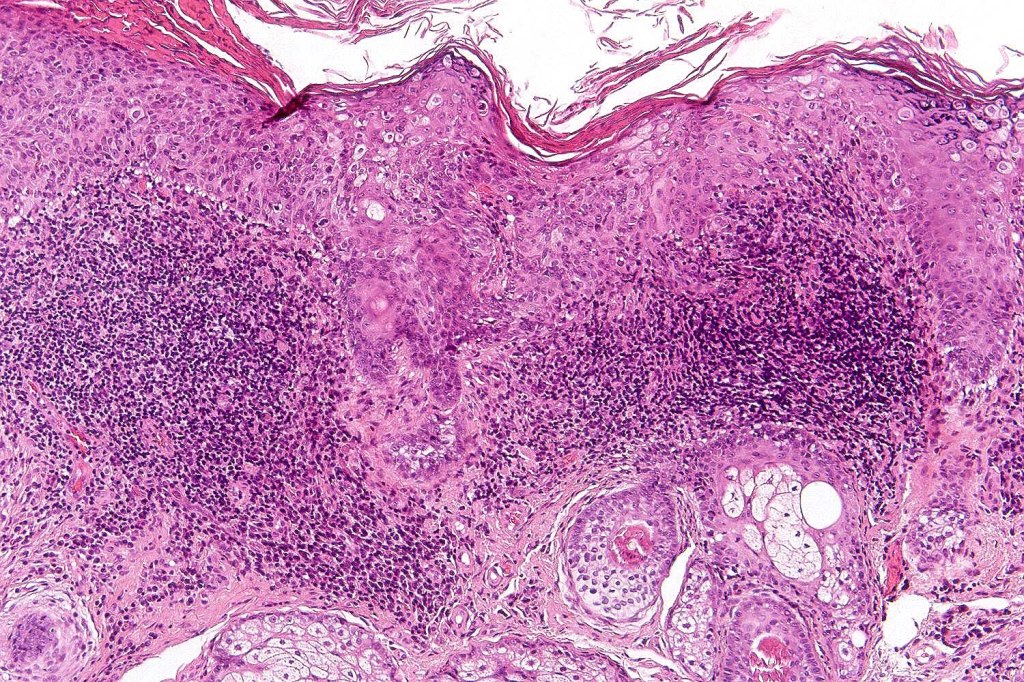

Histological features

•Although a variety of subtypes are recognized, all are characterized by varying degrees of epidermal dysplasia

•Hyperkeratotic/hyperplastic actinic keratosis represents the prototype-alternating hyperkeratosis & parakeratosis- the former overlies the follicular & sweat duct ostia (Freudenthal funnel) while the latter overlies the interadnexal dysplastic epithelium & ranges from basal cell layer though to full thickness dysplasia (Bowenoid actinic keratosis); budding from the epidermis is a common finding; dysplastic epithelium commonly forms a mantle around the follicles and superficial sweat ducts

•Variable lack of maturation, nuclear irregularity, pleomorphism & mitotic activity

.Superficial dermal lymphohistiocytic infiltrate